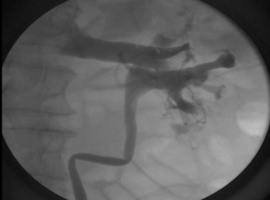

An Exceptionally Rare Retrograde Pyelogram Finding with an Unexpected Cause

Volume 8, Issue 1

:

Read More